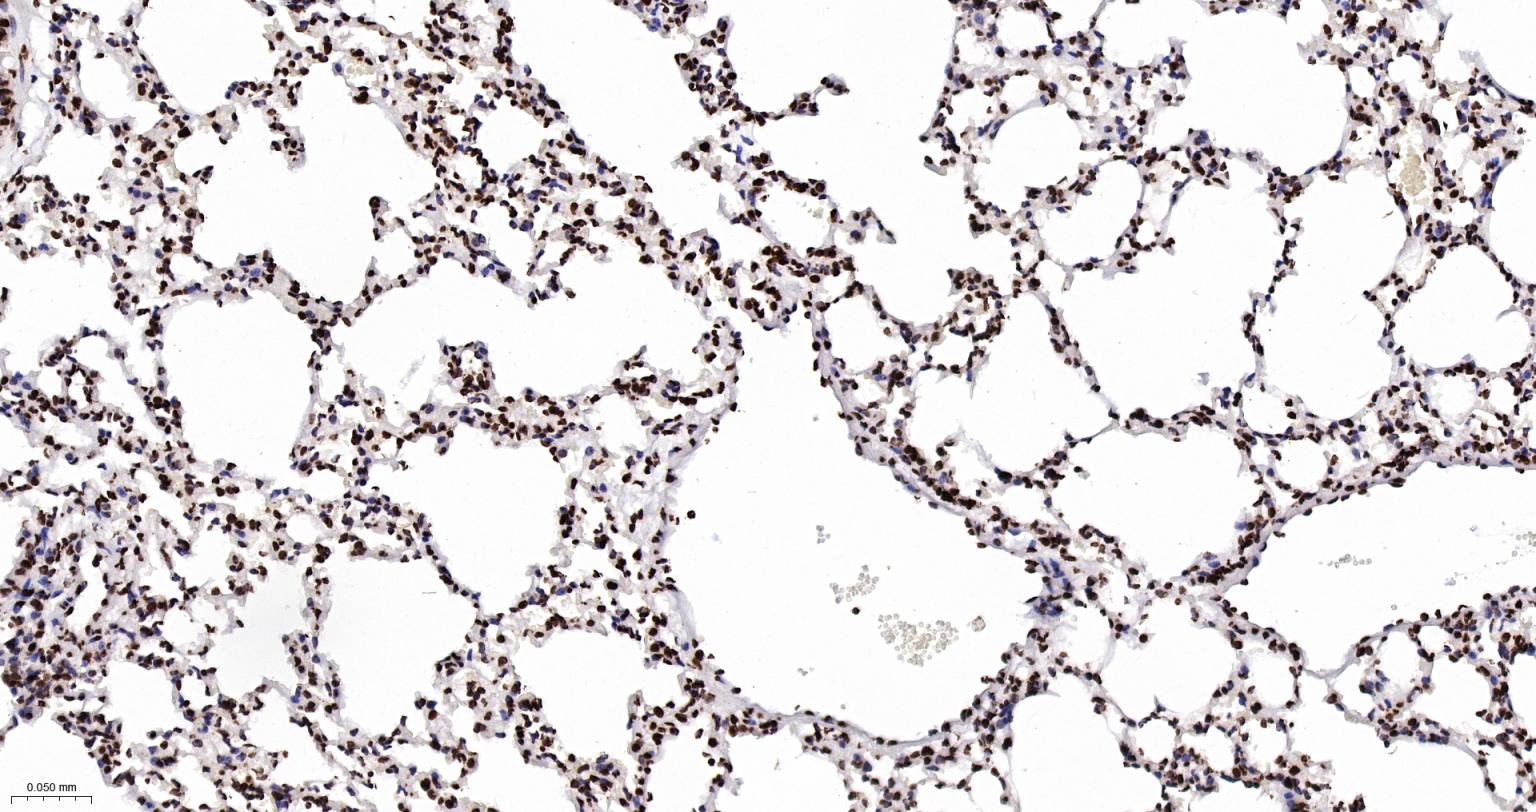

Paraformaldehyde-fixed, paraffin embedded Human Lung; Antigen retrieval by boiling in sodium citrate buffer (pH6.0) for 15 min; Antibody incubation with Histone H2A.X Monoclonal Antibody, Unconjugated(bsm-61080R) at 1:200 overnight at 4°C, followed by conjugation to the SP Kit(Rabbit, SP-0023) and DAB (C-0010) staining.

Paraformaldehyde-fixed, paraffin embedded Mouse Lung; Antigen retrieval by boiling in sodium citrate buffer (pH6.0) for 15 min; Antibody incubation with Histone H2A.X Monoclonal Antibody, Unconjugated(bsm-61080R) at 1:200 overnight at 4°C, followed by conjugation to the SP Kit(Rabbit, SP-0023) and DAB (C-0010) staining.

Paraformaldehyde-fixed, paraffin embedded Rat Lung; Antigen retrieval by boiling in sodium citrate buffer (pH6.0) for 15 min; Antibody incubation with Histone H2A.X Monoclonal Antibody, Unconjugated(bsm-61080R) at 1:200 overnight at 4°C, followed by conjugation to the SP Kit(Rabbit, SP-0023) and DAB (C-0010) staining.